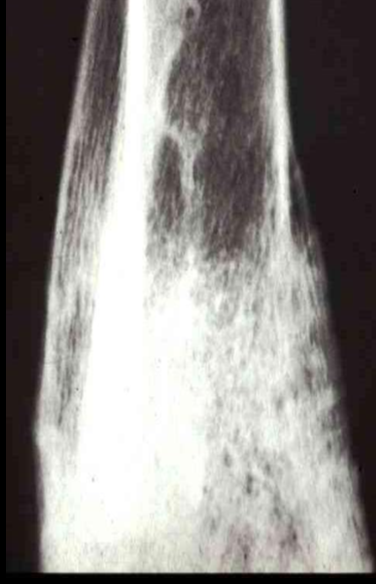

Permeative lysis

Permeative lysis and a fracture